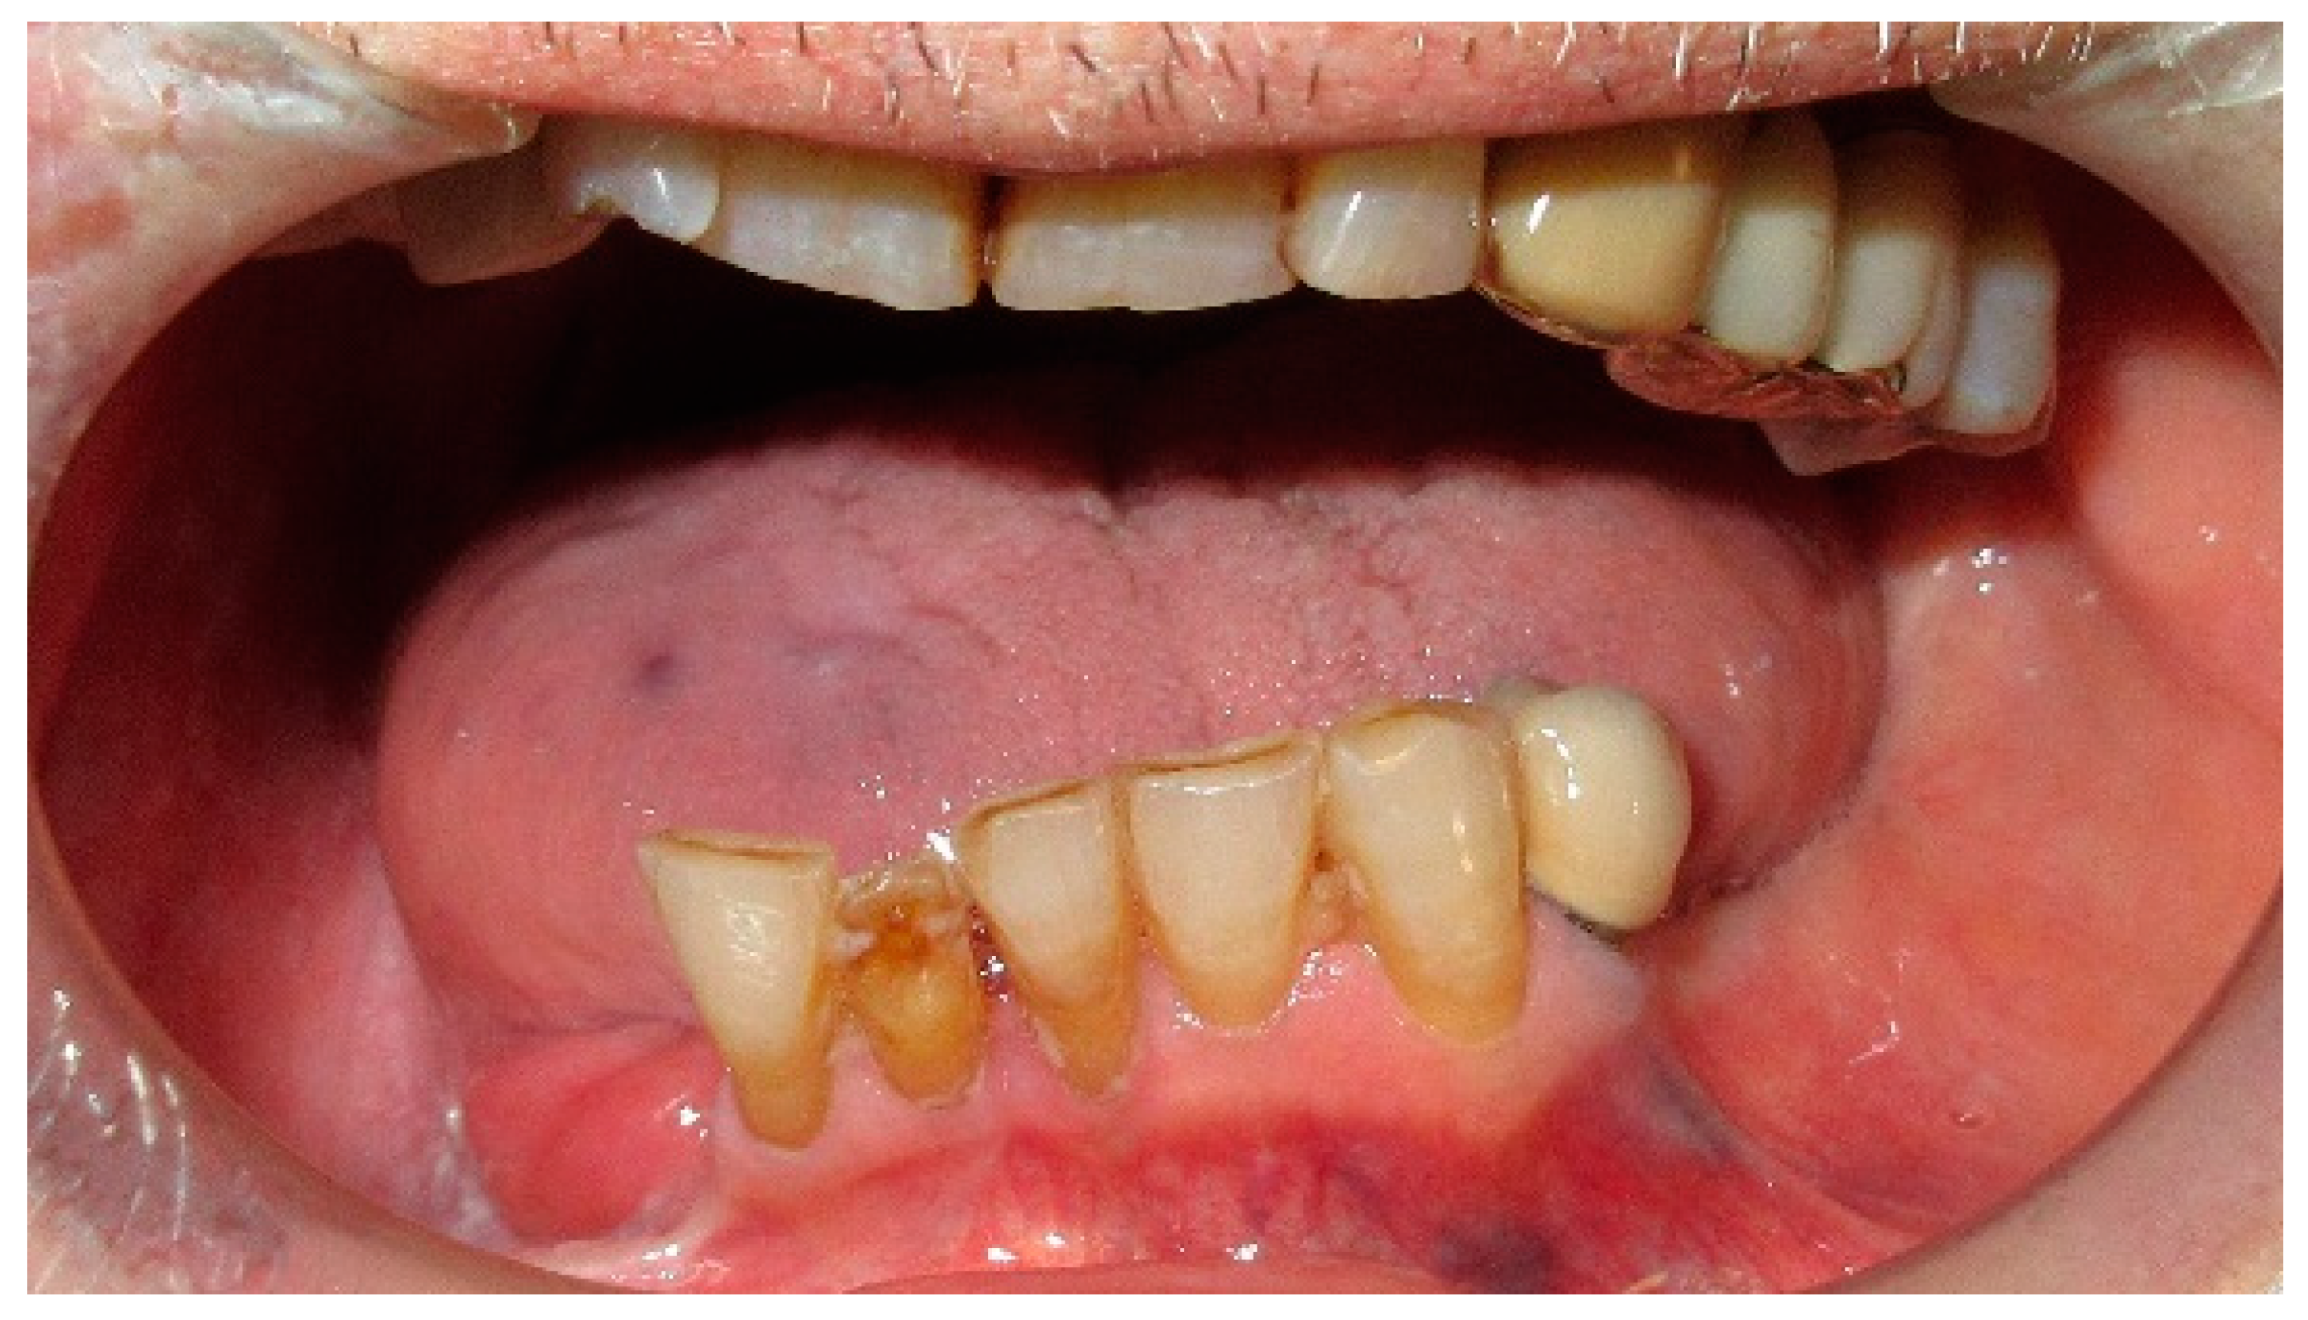

The patient of case 5 displayed a moderate latero-deviation following an L2-3 hemimandibulectomy with partial resection of the coronoid process (Figure 21 and Figure 22). Photos of interocclusal contact between the upper and lower teeth were not feasible due to the patient being unable to successfully close her mouth with the dental gag inserted.

The patient’s surviving teeth (32, 33, 34, 35) are not sufficient to stabilize and counteract the deviation towards the affected side, which not only develops on the transverse plane (left to right) but also on the frontal plane (back to front).